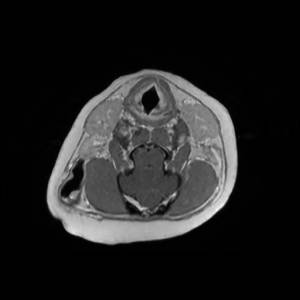

Main Gallery

Playing with a photo gallery function. It is possible to have multiple galleries, each within a namespace.